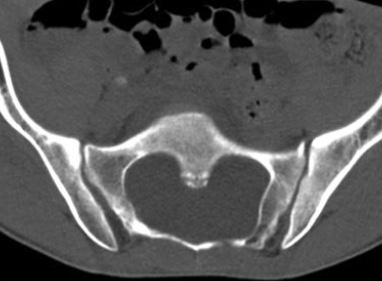

- Ectasie durale (en général peu symptomatique)